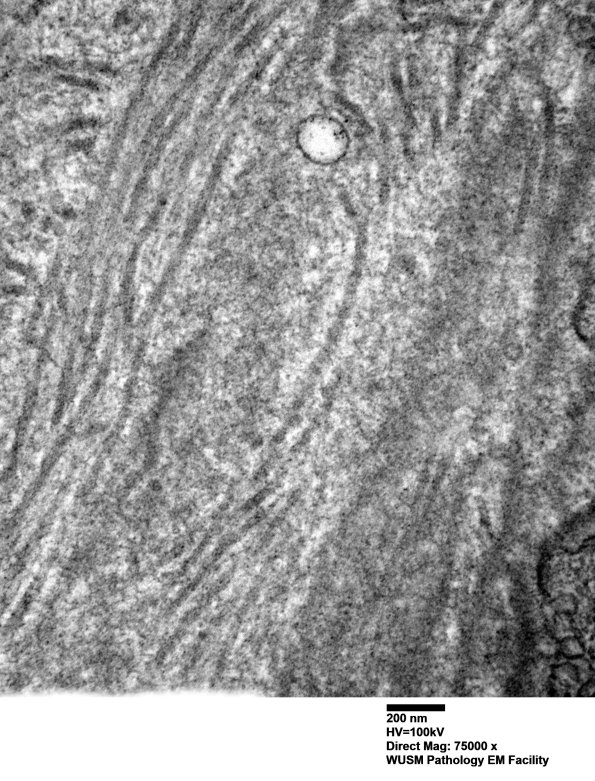

Washington University Experience | VASCULAR | Hypoxia-Ischemia, fetal-neonatal | White Matter | 14B1D (Case 14) EM006 - Copy

14B1D (Case 14) EM006 - Copy